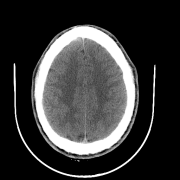

We also include visual examples of consecutive CT slices in Fig. 3. In Scan 1, the baseline Att-MIL produces a wrong prediction at scan level. When using SA, the prediction is correct since dependencies between adjacent slices have been learned. In Scan 2, both models produce correct predictions at scan level, but SA-DMIL is more accurate at slice level. This occurs thanks to the SA loss, that turns the attention scores into smoother values and, therefore, avoids random jumps up and down the decision threshold.

| Scan 1 | ![]() |

| Ground truth | Normal | Normal | Normal | Normal | Normal | Normal | ||

| Att-MIL () [15] | ICH | ICH | Normal | ICH | Normal | ICH | ||

| SA-DMIL- () | Normal | Normal | Normal | Normal | Normal | Normal | ||